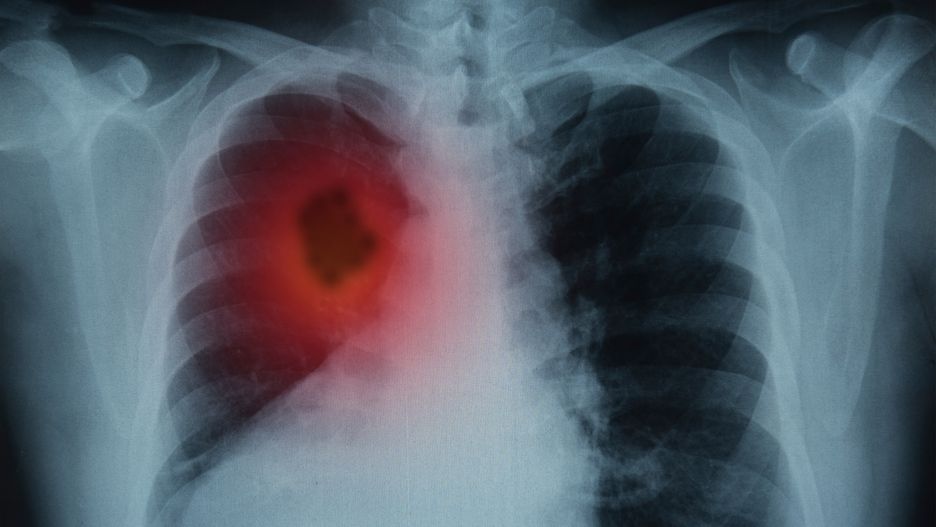

Objaw pojawia się na skórze. To znak, że w twoich płucach rozwija się rak

Rak płuc to nowotwór złośliwy, który na początku nie daje żadnych charakterystycznych symptomów. W zaawansowanym stadium rozwoju choroby pacjenci skarżą się na kaszel, problemy z oddychaniem i krwioplucie. Bardziej nietypowe objawy tego nowotworu można zauważyć na skórze. Sprawdź jakie.

Pamiętajmy, że im wcześniej nowotwór zostanie zdiagnozowany, tym większa szansa na powrót do zdrowia. Dlatego żadnego z wyżej wymienionych objawów skórnych nie wolno bagatelizować. Dotyczy to zwłaszcza osób palących papierosy.